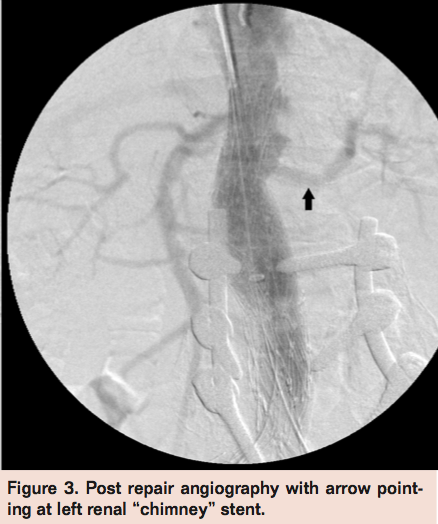

Next, simultaneous balloon inflation of the graft and the “chimney” stent was done. After this, an angiogram revealed a filling of the aortic sac consistent with type I proximal endoleak. A Palmaz stent was deployed proximally partially into the aortic cuff and partially into the native aorta to eliminate any infolding of the graft that may have been responsible for the endoleak. In order to avoid crushing the ICAST stent, a simultaneous balloon was inflated in the ICAST stent while the Palmaz stent was being deployed. The final angiogram revealed adequate seal with no evidence of endoleak and good perfusion of bilateral renal arteries (Figure 3).